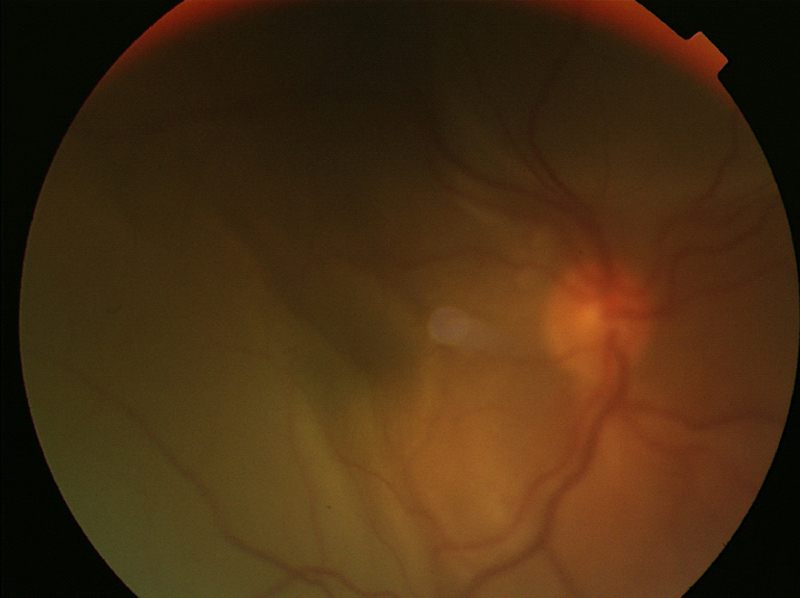

La fase uveítica aguda dura de 2 a 6 semanas y se caracteriza por DR bilateral (Figuras 1, 2 y 3).

Figura 1. Imagen DR seroso en el V-K-H.